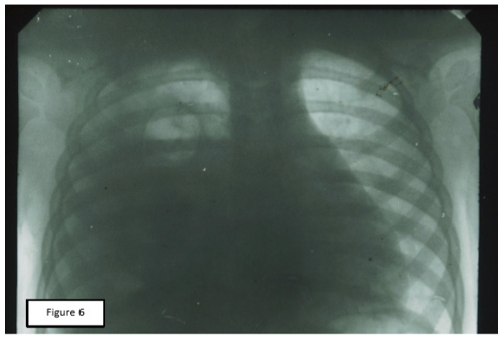

Figure 6: Rheogram of pulsatory blood flow of the same patient. 1: The source RPG; 2: RPG after cupping therapy; A: Differential RPGs; Б: Main RPG; В: Phonocardiogram.

The result of these intentions were the records of comparative RPGs, which can serve as objective evidence of the pathogenic effectiveness of CVB and СupТ. The analysis of the obtained records allowed us to note that, despite the fundamental differences in the place of application and technique of these two procedures, their final results were almost the same. The values of RR and MV after the procedure decreased significantly, although RV remained unchanged. Performance SA, MBF has changed markedly, HR decreased to a lesser extent. In General, the data obtained showed a significant decrease in hyperventilation and improved perfusion. Baseline values of RPG indicated a marked predominance of ventilation over blood flow. After treatment, the ratio between these parameters (Kv/p) was equalized. This point was accompanied by a significant improvement in the condition and well-being of patients. A visual representation of change records RPG under the influence of СupT gives a comparative picture of these curves, which were recorded from one of our patients (Figures 5 & 6).